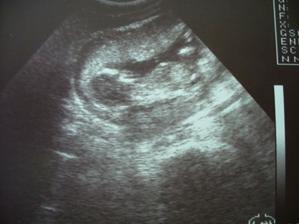

Zadařilo se

po dlouhé době se zadařilo, ve čtvrtek. tj. 18.6. 2009 jdeme k doktorce potvrdit těhu,.těhu potvrzeno.